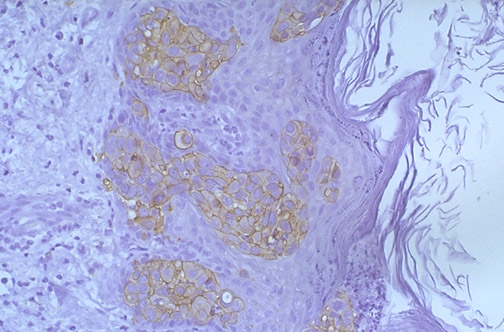

Here is a C-erbB-2 (HER2-neu) positive Paget's disease of breast seen under medium power. Note the perimembranous staining pattern (cytoplasmic staining is nonspecific).